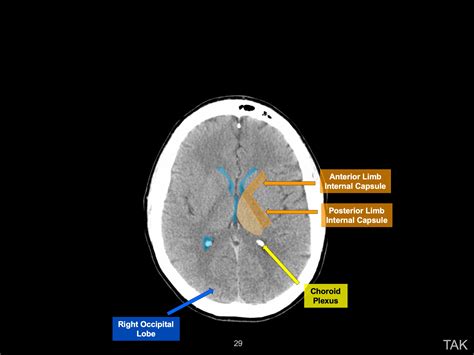

Interpreting a Normal CT of Brain

Interpreting a normal CT of brain involves looking for specific features that indicate the absence of abnormalities. Key elements that radiologists examine include:

• Brain Tissue: The brain tissue should appear uniform and without any signs of swelling, bleeding, or tumors.

• Ventricles: The ventricles, which are fluid-filled spaces within the brain, should be of normal size and shape.

• Blood Vessels: The blood vessels should be clear and free of any blockages or aneurysms.

• Skull and Bones: The skull and surrounding bones should be intact and without fractures or other abnormalities.